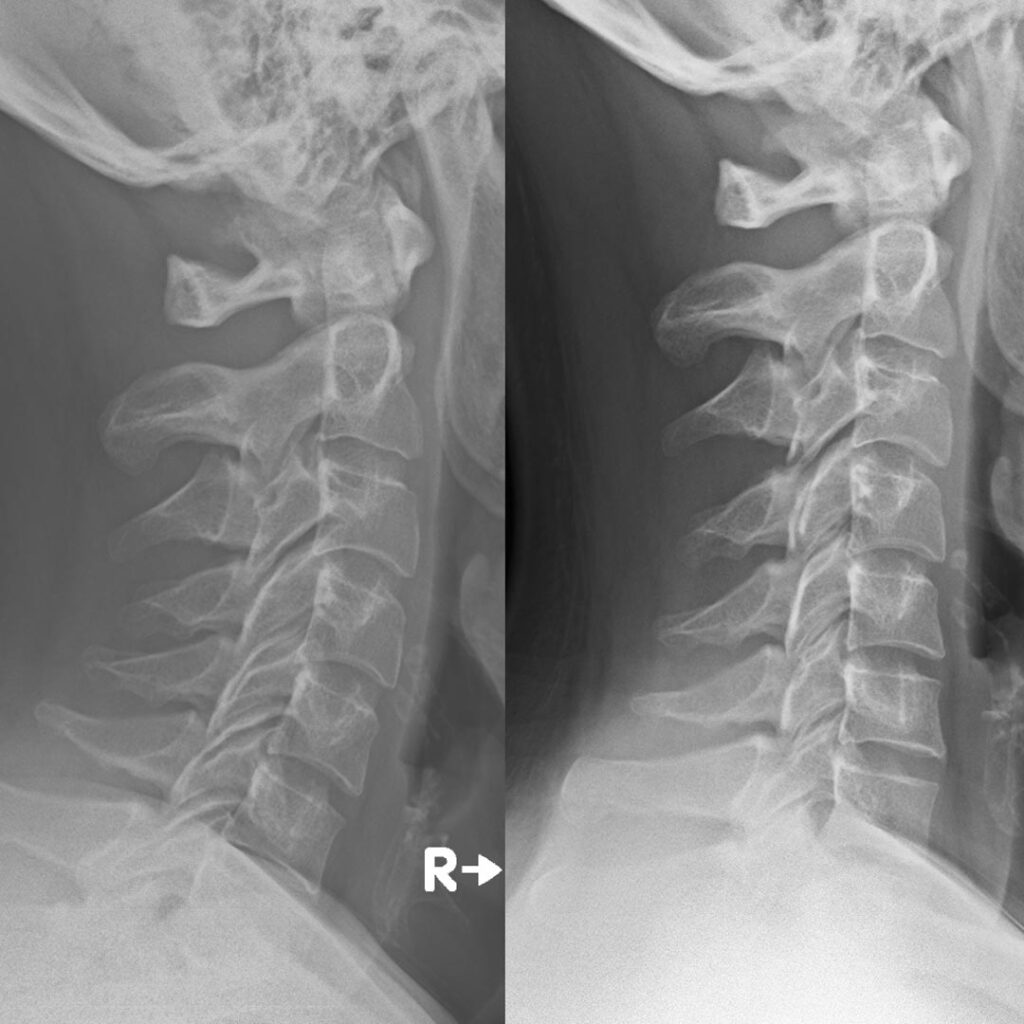

Vi er ikke ens, og derfor sørger vi altid for en grundig forundersøgelse inden vi går i gang med den egentlige kiropraktik. Vi ser på hele din krop, og behandler kun det vi kan se, hvilket betyder, at der ligger røntgenbilleder til grund for hvert behandlingsforløb. Hos os er du i trygge hænder.

Forbedring af nakkekurve

Bedre Holdning

Nakkekurven blev bedre

september 6, 2025